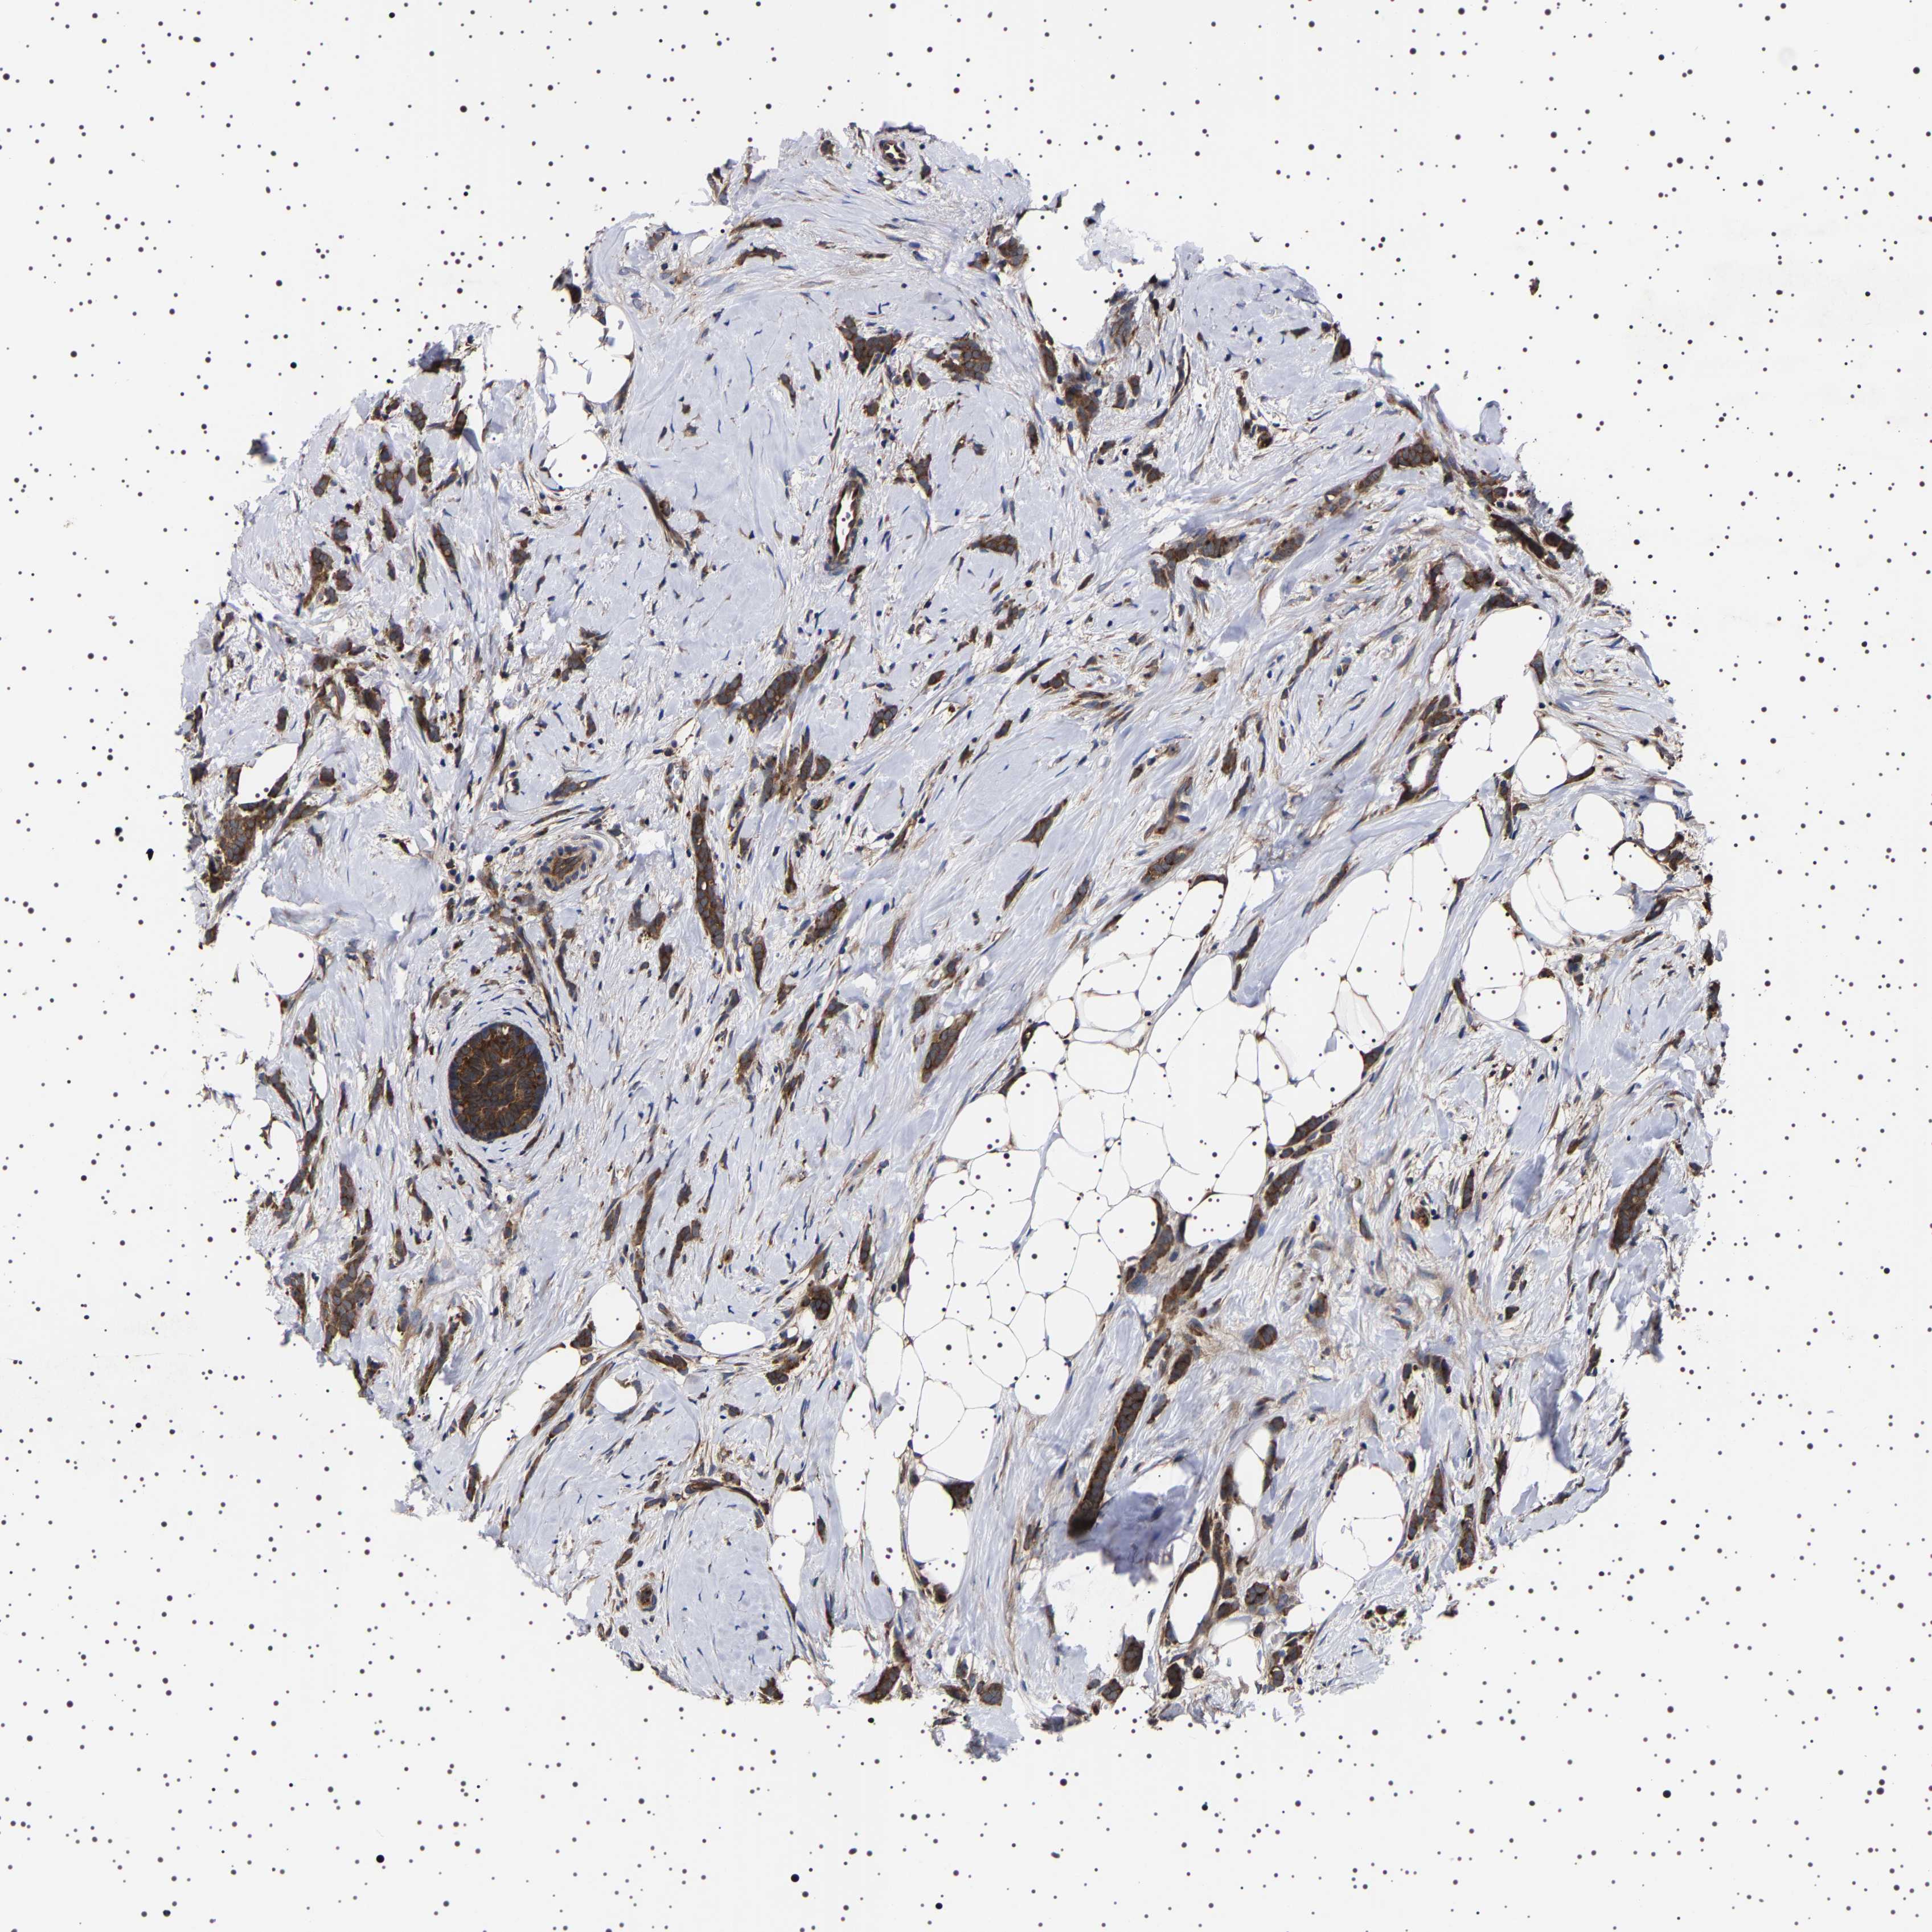

CANCER BREAST CANCER Show tissue menu

BRCA TCGA BRCA VALIDATION PROTEIN EXPRESSION